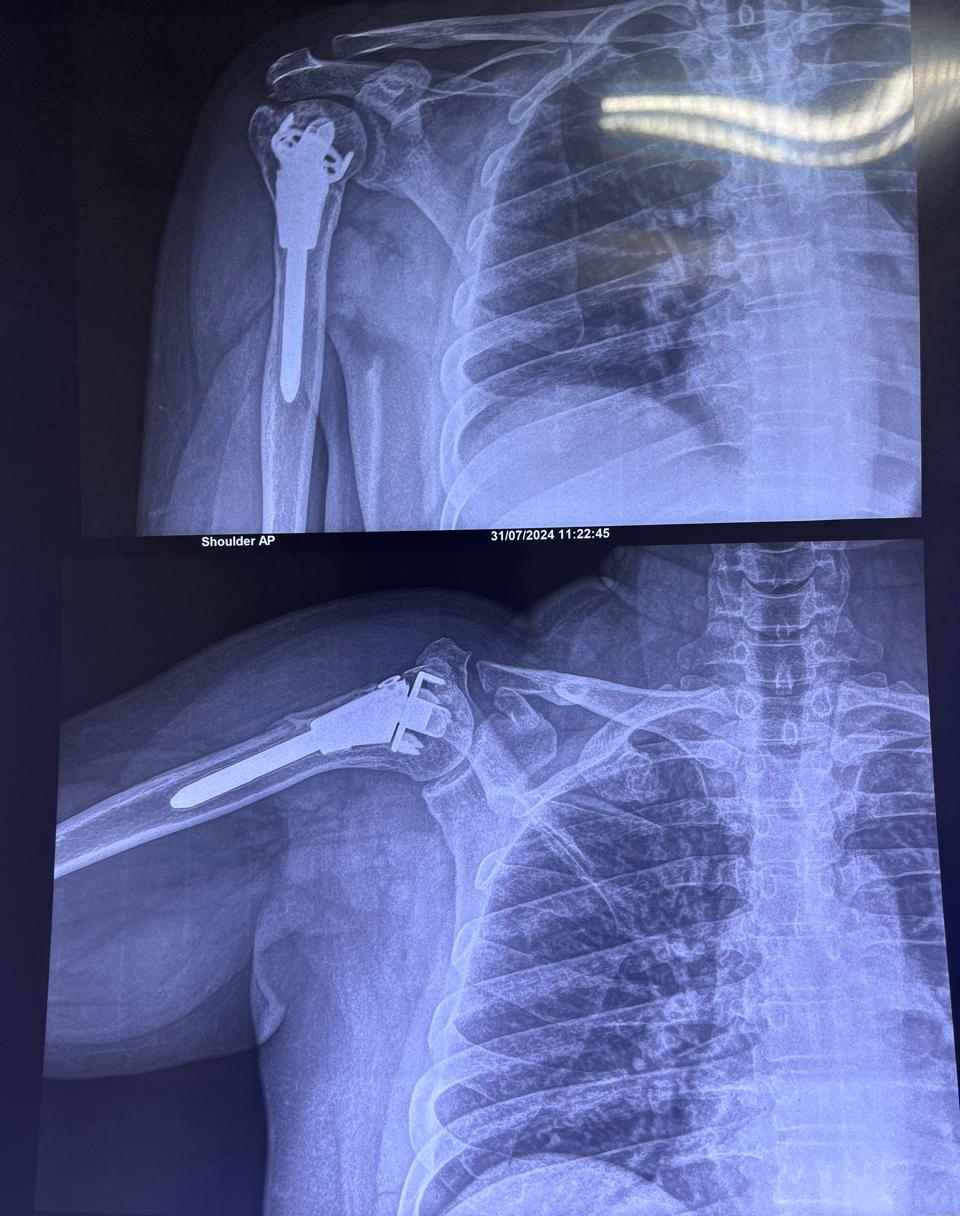

X-ray left shoulder external rotation ap view of SMT Indumati in 414A

Shoulder Surgery

State new method of fixation of upper end humerus fracture using just unik